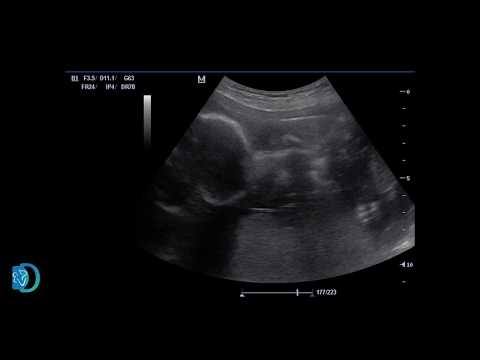

ჭიპლარის ვენაში სისხლის გადასხმა / INTRAUTERINE TRANSABDOMINAL BLOOD TRASNSFUSION

ჭიპლარის ვენაში სისხლის გადასხმა / INTRAUTERINE TRANSABDOMINAL BLOOD TRASNSFUSION 03:48

ჭიპლარის ვენაში სისხლის გადასხმა / INTRAUTERINE TR...